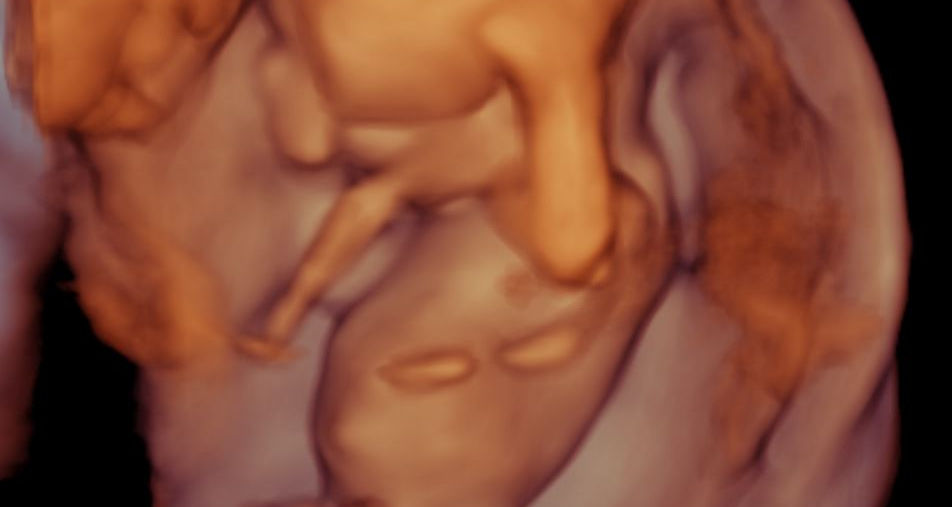

El Eco Cromosómico (Marcadores Genéticos) en Quito, realizado entre la semana 11 y 13.6 de embarazo, es un estudio de vital importancia para la salud de tu bebé.

Esta ecografía especializada no solo confirma la vitalidad y edad gestacional, sino que se enfoca en la evaluación de marcadores clave como la translucencia nucal (TN), la presencia del hueso nasal, Morfología de la onda de Ductus venoso, Regurgitación Tricuspidea y más. Estos indicadores son fundamentales para estimar el riesgo de anomalías cromosómicas, como el síndrome de Down, y otras condiciones fetales.

3D- 4D - 5D, Cervicometría